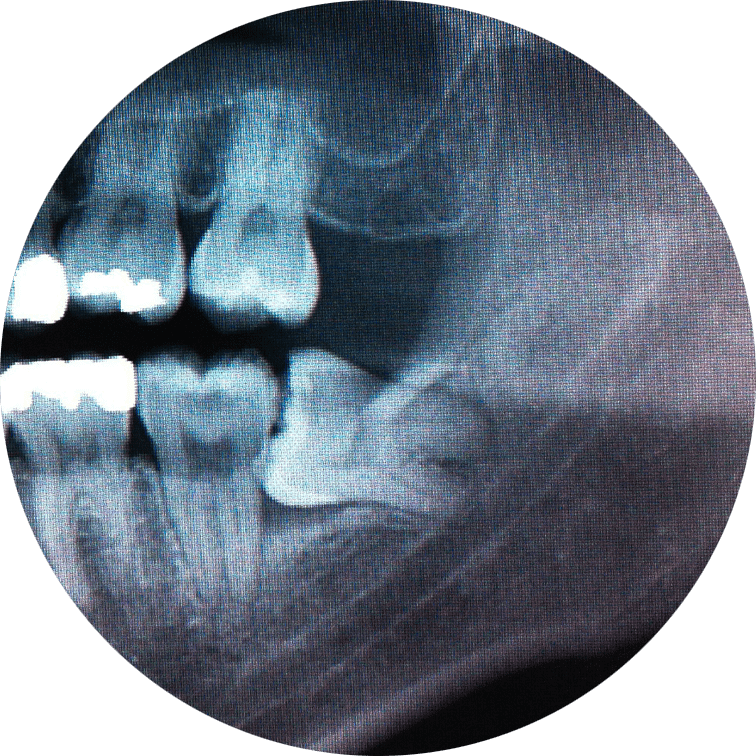

Wisdom Tooth Extractions

Wisdom teeth typically come in during our teenage years. Often, though, they fail to break completely through the gums or erupt at an awkward angle. These teeth can press against other healthy teeth and cause those teeth to grow crooked. Wisdom teeth are also notoriously difficult to clean, which makes them prone to decay. We’ve extracted thousands of impacted wisdom teeth over the years with great success. If wisdom teeth are causing pain or overcrowding in your mouth, it may be time to take them out! Our team will confirm this and schedule you for the next available surgical appointment.